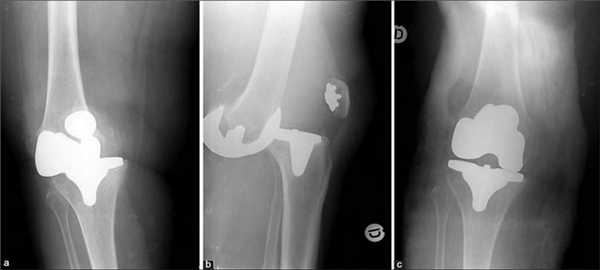

Согласно диагнозу, возрастным и весовым критериям, физическим данным и сопутствующим заболеваниям, специалист выбирает наиболее эффективную тактику имплантации:

- - протезированию подлежит только одна из полукруглых возвышенностей бедренной кости с подлежащим к ней проксимальным фрагментом большеберцовой кости (применяется у пожилых пациентов и у лиц с низкой физической активностью);

- тотальная операция (полная) - меняется весь коленный сустав, он удаляется полностью, а на его место имплантируется эндопротез;

Неполные имплантаты, устанавливаемые при частичной замене, имеют короткий срок эксплуатации. Такие модели вырабатываются в 2 раза быстрее, чем тотальные конструкции, при этом их потенциал прочности не рассчитан на высокой степени физические нагрузки. Преимущества частичного протезирования состоят в том, что замещается имплантатом только определенная часть сочленения, остальная область остается нетронутой. Таким образом, щадящее вмешательство позволяет сократить сроки реабилитации и перенести восстановительный период относительно легко.

Две техники операции у одного пациента.